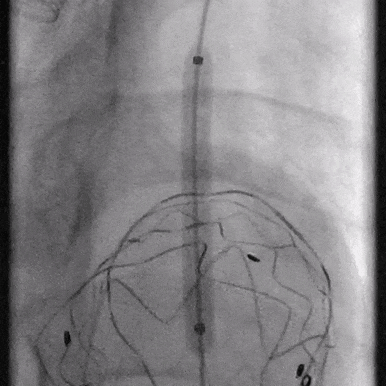

03. 控制性降压至90/55mmHg左右,沿右股动脉入路引入超硬导丝及华脉泰科胸主支架PTBS3430180,术中沿LCCA后缘处缓慢释放1-2节,再次造影确认定位精准后继续释放主体支架,造影示覆膜支架未覆盖LCCA,覆盖LSA。

04. 沿左肱动脉引入5F Ver导管,头端垂直抵住主体支架覆膜,引入0.035″长泥鳅导丝配合导管顺利破膜,进入主动脉。

05. 0.035″长泥鳅导丝进一步超选进入降主动脉段,并沿右股动脉引入抓捕器抓取泥鳅导丝建立导丝路径,依次逐级使用4*40mm、6*40mm、8*40mm Amanda球囊扩张破膜处。期间可见明显受压切迹影。

06. 沿右股动脉引入8F长鞘,置入8*50mm Viabahn覆膜支架于开窗处,远端避开左椎动脉,近端超过覆膜支架1cm并完成释放。

07. 最后行全主动脉造影示LSA开窗支架重建良好,近端主体支架定位显影良好,腹主动脉右肾动脉、腹腔干动脉及肠系膜上动脉显影较支架植入前明显改善。